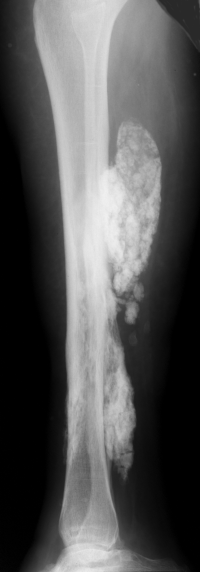

Osteofibrous dysplasia tibia. Typical anterior diaphyseal location, mixed lesion with minor anterior bowing. In an adult the differential diagnosis would include an adamantinoma.

10-year-old girl with mild pain and deformity of the shin.